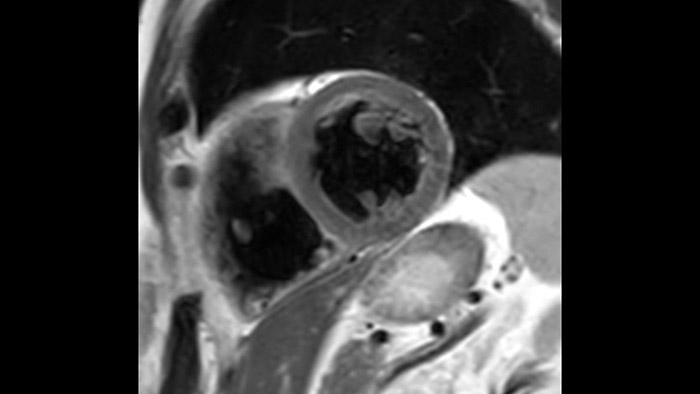

Today's diagnostics often cannot detect heart dysfunction until symptoms occur. MyoStrain utilises segmental strain to measure 48 segments of the heart and provides physicians with a unique diagnostic tool to help identify regional dysfunction before the heart as a whole is affected.

IntelliSpace Portal MR Caas5,6 Strain7 assists in patient diagnosis and monitoring by providing global strain parameters such as global longitudinal strain (GLS), global circumferential strain (GCS), and global radial strain (GRS), using short and long axis MR images, as well as describing the myocardium deformation- such as shortening, thickening, and lengthening during the cardiac cycle.